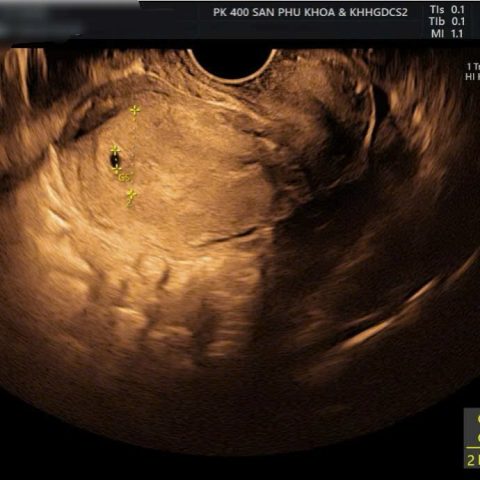

Thai sớm trong tử cung chính là hình ảnh túi thai mới hình thành, chưa rõ cấu trúc của thai, chưa định rõ được tuổi thai và thường dưới 4 tuần tuổi. Thai sớm trong tử cung có thể được phát hiện dưới siêu âm, trước đây với kỹ thuật siêu âm đường bụng thì rất khó có thể phát hiện được túi thai sớm. Tuy nhiên ngày nay nhờ kỹ thuật siêu âm qua đầu dò âm đạo với độ phân giải hình ảnh cao hơn nên thường phát hiện được thai sớm.

- Siêu âm tử cung và phần phụ: Những dấu hiệu trên siêu âm có thể thấy ở thai kỳ sớm là thấy tử cung tăng kích thước hơn bình thường, niêm mạc tử cung dày, có thể thấy hình ảnh túi thai sớm trong lòng tử cung. Túi thai sớm trong lòng tử cung là gì? Chính là một cấu trúc bên trong lòng tử cung với ECHO trống nghĩa là túi trống âm, không rõ cấu trúc bên trong và kích thước thường rất nhỏ chỉ vài mm và một số trường hợp thai đôi khác trứng còn có thể thấy hình ảnh hai túi thai. Thường thì túi thai sớm được phát hiện thông qua siêu âm đầu dò âm đạo.